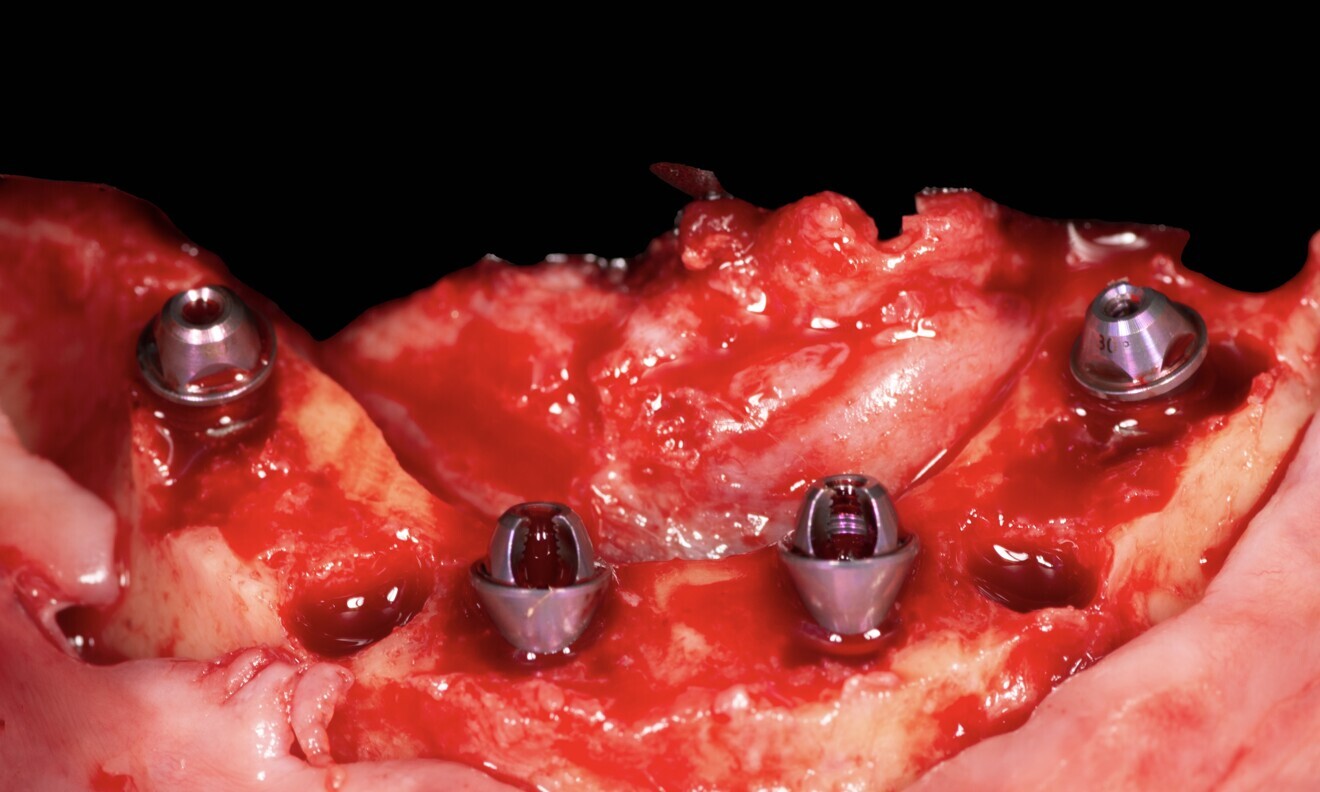

The treatment was carried out under local anaesthesia with 2% lidocaine and 1:100,000 adrenaline. A crestal incision was made and a full-thickness mucoperiosteal flap raised. The implant beds were prepared with the Straumann Surgical Cassette, and two Straumann BLX implants (4.5 × 10.0 mm, SLActive, Roxolid) and two Straumann zygomatic implants (4.3 × 40.0 mm) were placed in the maxilla (Fig. 8). Following the same protocol, four Straumann BLX implants (4.5 × 10.0 mm, SLActive, Roxolid) were inserted in the mandible. Straumann screw-retained abutments were positioned on to the implants (Fig. 9).

Fig. 8